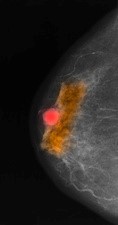

маммографическая картина рака молочной железы с компьютерной обработкой изображения.